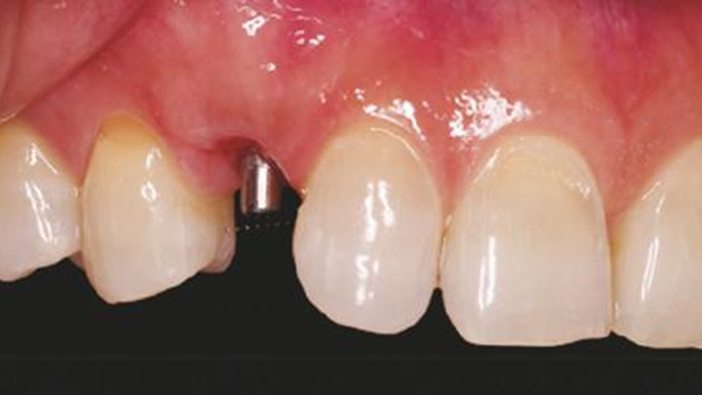

Clinical case: BPET PREDICTABILITY - State-of-the-Art SOCKET SHIELD

- Courtesy of Dr. Howard Gluckman, South Africa -

“AnyRidge is perfect for the anterior esthetic zone due to its strong initial stability & fast osseointegration.

Plus, KnifeThread® ensures space maintenance when using the PET/Socket Shield/Root Membrane Technique, showing excellent bone growth.”